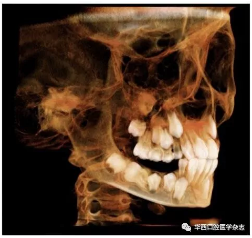

全景片及錐形束CT(cone beam computed tomo-graphy,CBCT)三維重建影像顯示:46牙胚存在,牙冠朝向遠中,且牙長軸與下頜骨下緣接近平行,遠中根發(fā)育約為根長2/3,近中根發(fā)育約為根長1/2且稍向下彎曲,近中根與45牙關系密切,下頜其余牙胚正常(圖2、圖3)。

圖 3 治療前CBCT三維重建